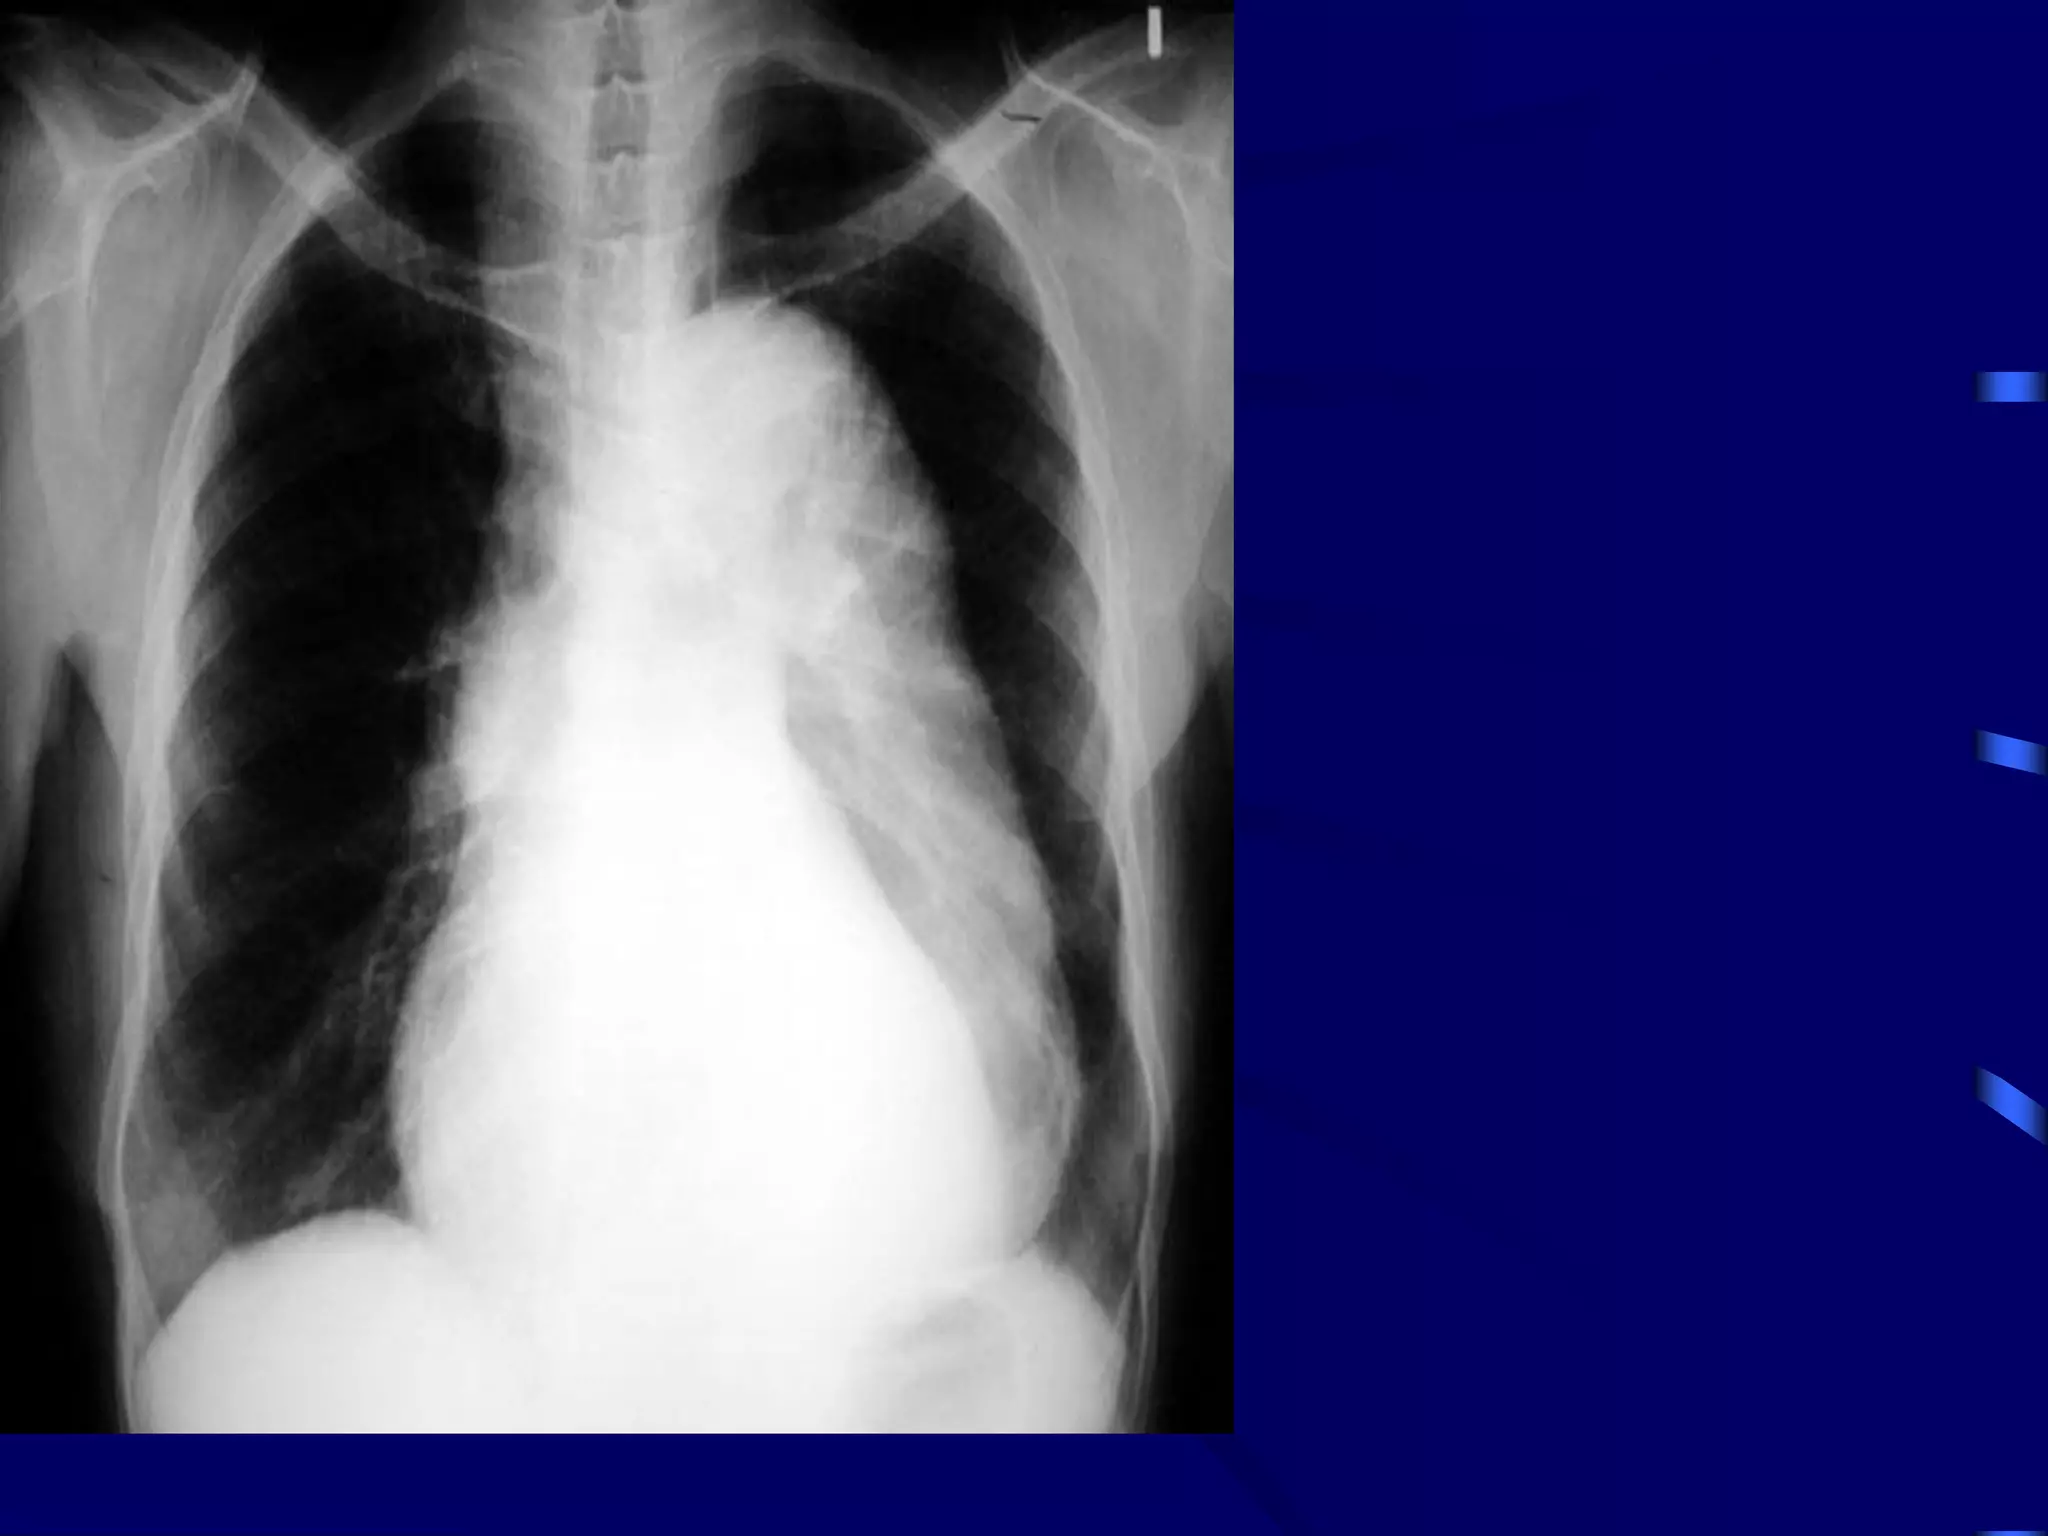

Miliary Tuberculosis

Produced by acute dissemination of tubercle

bacilli via the blood stream.The term miliary

derives from the radiological picture of

diffuse, discrete nodular shadows about the

size of millet seed (2mm).

A- Classical form:

Clinical features:

Diasnosis:

1) Clinical.

2) Xray.